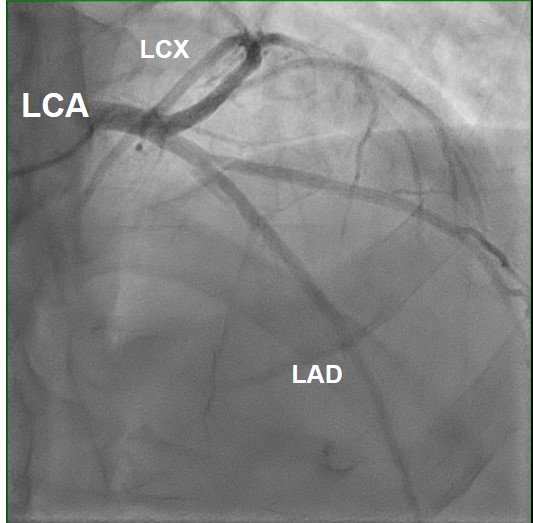

Koronarangiographie

Kein Nachweis relevanter Gefäßstenosen